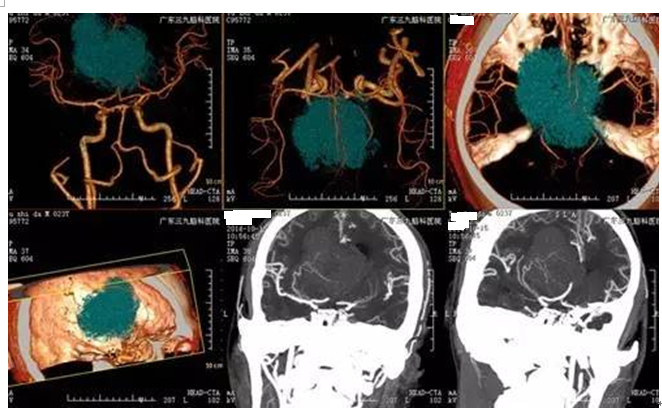

▲术前CTA显示肿瘤位置、血供情况

中枢神经细胞瘤多为良性或低度恶性,预后良好,部分预后较差。手术切除全部肿瘤是中枢神经细胞瘤的首选治疗方法。手术切除的目的主要在于解除梗阻性脑积水,全切术后并发症较多,但整体治愈率高。中枢神经细胞瘤对放疗极为敏感有效,结合术后放疗可获得长期生存。本例肿瘤体积较大,与侧脑室壁、丘脑、下丘脑及大脑大静脉等中线结构紧邻,虽然术中血供丰富,切除肿瘤困难,但是做到了全切肿瘤。术后恢复良好,未有明确并发症出现。术中造瘘(脚间池、四叠体池)避免了分流手术。